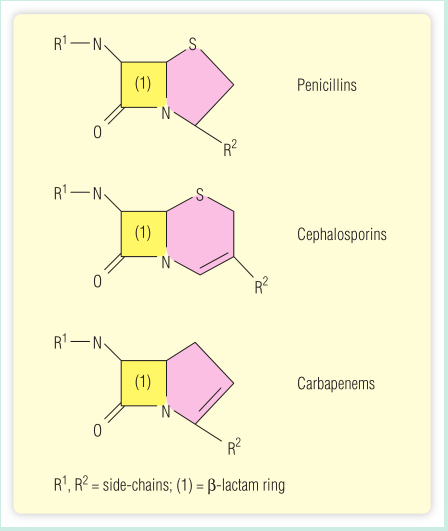

BOX 5.1 药物过敏-免疫球蛋白E交叉反应

一名58岁的妇女被诊断出患有肺炎,急需抗生素。约20年前,医生给她开了青霉素治疗喉咙痛,在她服用第一粒胶囊后的30分钟内,她出现广泛的皮疹,呼吸困难,休克。她的主治医生认为可能是青霉素过敏发作。医生知道,青霉素过敏的人不应该再接受青霉素治疗,并且对β-内酰胺类的其他抗生素,如一些头孢菌素和碳青霉烯类也会有大约5%到10%的反应风险。他决定用红霉素治疗病人,红霉素的分子结构和青霉素非常不同。病人对这种抗生素反应良好,没有副作用。

药物的不良免疫反应,特别是抗生素,可能是一个重大的医学问题。青霉素可以与自身蛋白形成半抗原载体结合物,然后作为免疫原产生免疫球蛋白E(IgE)抗体。不幸的是,抗青霉素IgE抗体也会与其他一些抗生素发生交叉反应。这可能会使这些患者的细菌感染治疗复杂化,因为他们无法服用对抗感染所需的抗生素。

青霉素是一种β-内酰胺类抗生素,之所以这样命名,是因为它含有四元β-内酰胺环结构,如Fig 5.3所示。一些抗青霉素IgE抗体可以与其他结构相似的抗生素反应。具体的特异性可能会有所不同,但有足够的“适合度”(交叉反应性)可以显著结合这些其他的抗生素,并造成治疗问题(Fig 5.8)。

Fig 5.8 青霉素及其相关抗生素的结构。黄色的是β-内酰胺环